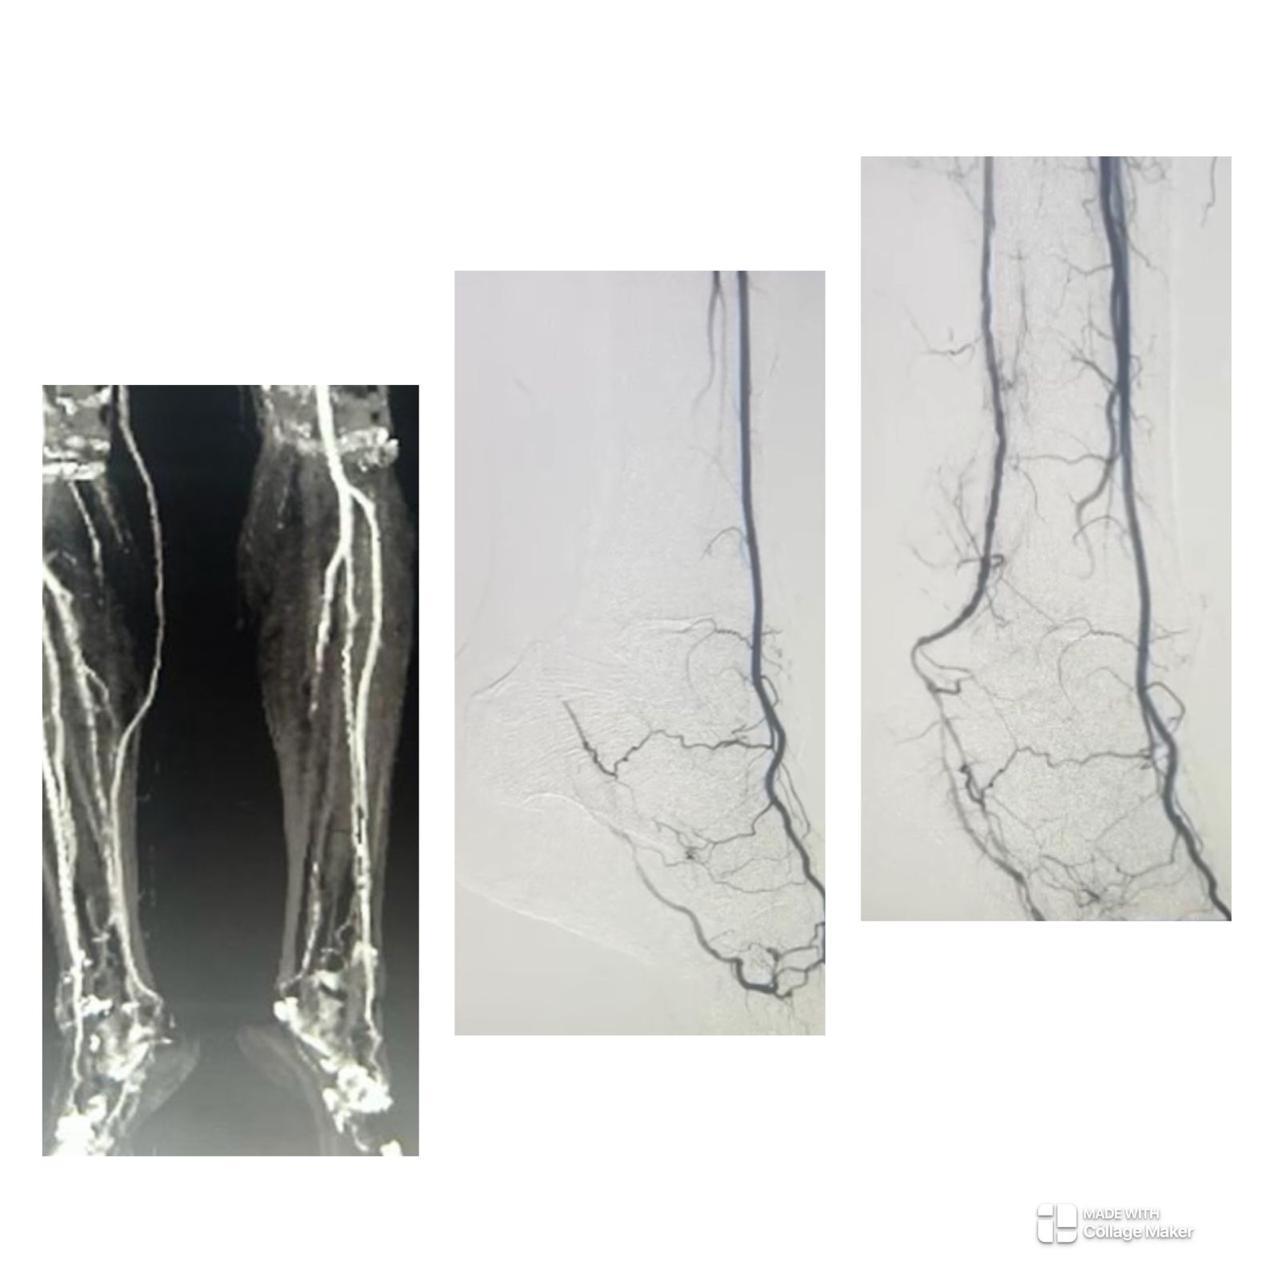

Peripheral Angioplasty procedure at Sarda Vascular Centre Dehradun

Interventional Radiology (IR) uses real-time imaging such as X-ray, ultrasound, CT, or MRI to guide tiny instruments through the body for treatment — without large surgical incisions.